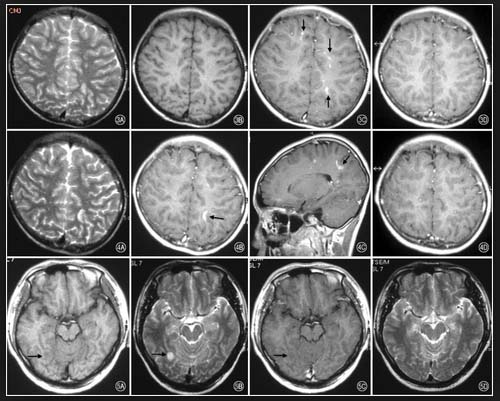

Một bệnh nhân nữ, doanh nhân 51 tuổi nhập viện với triệu chứng nhức đầu cả tuần, cô ta thường ưa thích các hải sản tái, sống ăn với mù tạt. 2 ngày trước nhập viện, bệnh nhân sốt cao > 39ºC, kèm theo nhức đầu và nôn mửa, người nổi ban đỏ, ngứa nhưng vẫn hoàn toàn tỉnh táo. Trước đó bệnh nhân đã khám tại bệnh viện tâm thần do chứng đau đầu liên tục, huyết áp ổn định, không có bệnh lý rối loạn chuyển hóa không thuyên giảm. Sau đó về khoa truyền nhiễm BVĐK tỉnh, ngày vào viện cho thấy có dấu hiệu nhức đầu nghiêm trọng, cứng cổ, dị cảm hai chi dưới, chọc dò tủy sống áp lực mở 240mmH2O, dịch não tủy không màu, trong suốt, bạch cầu 856 x 106 tế bào/L, protein 0,92g/L protein, glucose 1,7mmol/L, bạch cầu ái toan 54%, lymphocytes 37%. Chụp CT scanner và MRI não bộ không có dấu bất thường. Chẩn đóa ban đầu nghĩ đến viêm não màng não do tác nhân ký sinh trùng, huyết thành chẩn đoán ELISA 6 tác nhân, cho kết quả duy nhất Gnathostoma spinigerum dương tính 17 NTU hay OD = 1.26. Bệnh nhân được điều trị với thuốc albendazole liệu trình 3 tuần và corticosteroides 6 ngày, thuyên giảm và ra viện với kết quả xét nghiệm bình thường và lâm sàng cải thiện đáng kể vào ngày 26 kể từ khi nhập viện.

Việc chẩn đoán bệnh ANS dựa vào phần lớn tiền sử phơi nhiễm trước đó, đặc điểm lâm sàng và tăng BCAT trong dịch não tủy. Tăng BCAT trong máu ngoại vi có thể hiển thị. Các chỉ điểm cận lâm sàng của DNT về bệnh ANS gồm có dịch có vẩn đục, đám mây, áp lực mở tăng, protein tăng, nồng độ glucose bình thường và tăng số bạch cầu tuyệt đối với số BCAT tăng cao so với bình thường. Bệnh ANS thường không để lại các tổn thương tại chỗ qua hình ảnh CT scanner hoặc MRI não bộ.

Chẩn đoán bệnh GNS là môt thách thức. Sự tăng BCAT trong máu ngoại vi và trong DNT kèm với tiến sử du lịch đến các vùng có nguy cơ nhiễm cao và diễn tiến các triệu chứng sẽ giúp hỗ trợ cho chẩn đoán bệnh này. Tuy nhiên, sự vắng mặt dấu tăng BCAT đã được báo cáo trong một số ít bệnh nhân GNS.Phân tích mẫu bệnh phẩm DNT từ các bệnh nhân GNS thường cho thấy có nhiễm sắc vàng, một dấu hiệu tăng áp lực sọnão trong khoảng 50% số bệnh nhân, tăng lumpho bào kèm theo tăng BCAT, nồng độ glucose bình thường và protein có thể bình thường hoặc tăng. Chụp CT-scanner não bộ cho thấy hình ảnh tổn thương dạng nốt, các vùng xuất huyết với các vết và thậm chí gặp não úng thủy.

Chẩn đoán hình ảnh | CT scanner và MRI thường bình thường | CT scanner và MRI có thể dấu xuất huyết hoặc não úng thủy. |